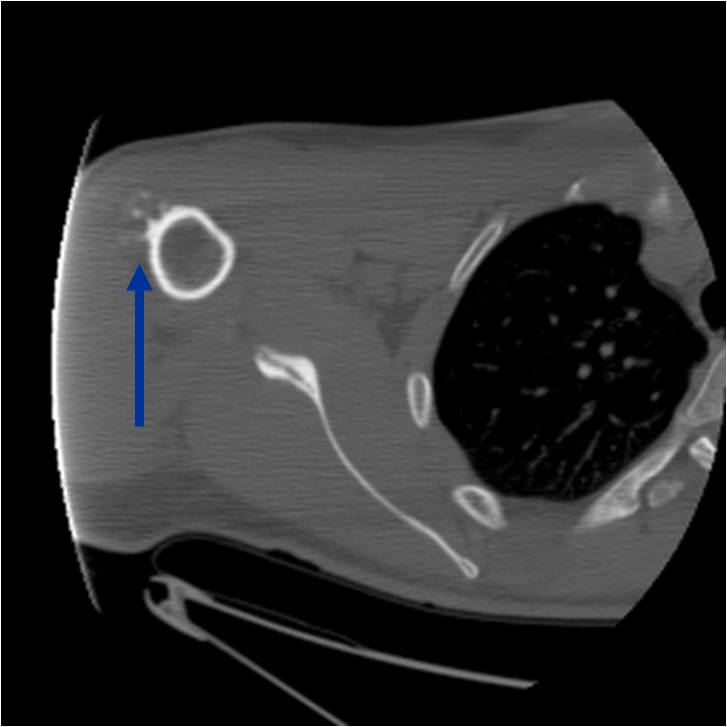

Radiographic Presentation

- Well circumscribed

- Appears to be embedded in underlying cortical bone

- Typically covered by a thin shell of reactive, often ossified periosteum

- Medullary cavity not grossly invaded